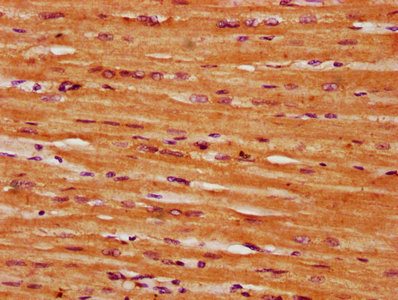

IHC image of CSB-PA020835LA01HU diluted at 1:300 and staining in paraffin-embedded human heart tissue performed on a Leica BondTM system. After dewaxing and hydration, antigen retrieval was mediated by high pressure in a citrate buffer (pH 6.0). Section was blocked with 10% normal goat serum 30min at RT. Then primary antibody (1% BSA) was incubated at 4°C overnight. The primary is detected by a biotinylated secondary antibody and visualized using an HRP conjugated SP system.